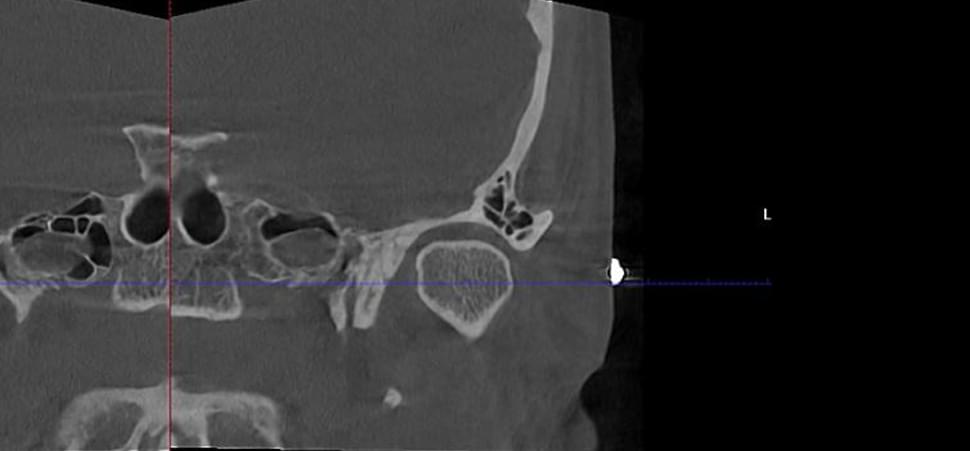

КТ скронево-нижньощелепних суглобів (СНЩС) — це найбільш інформативний метод дослідження рухомого з’єднання нижньої щелепи з черепом. На відміну від плоского панорамного знімка (ОПТГ), 3D-діагностика дозволяє побачити суглоб у стані спокою та при максимальному відкритті рота. Це дає можливість лікарю оцінити не лише структуру кістки, а й ширину суглобової щілини, положення суглобових голівок та симетрію їх руху.

✅ Що побачить лікар на КТ суглобів?

🔹 Анатомічні зміни: Деформацію суглобових поверхонь, наявність остеофітів (кісткових

розростань) або ознак артрозу та артриту.

🔹 Положення голівки суглоба: Чи правильно розташована суглобова голівка в ямці при закритому та

відкритому роті (виявлення підвивихів або дислокацій).

🔹 Стан кісткової тканини: Щільність кістки, наявність ерозій, кіст або наслідків травм

(тріщини, переломи).

🔹 Симетрія: Порівняльний аналіз правого та лівого суглобів, що критично важливо при порушеннях

прикусу або болях лише з одного боку.

🔹 Ширина суглобової щілини: Звуження або розширення простору, що вказує на запальні процеси або

проблеми з диском.